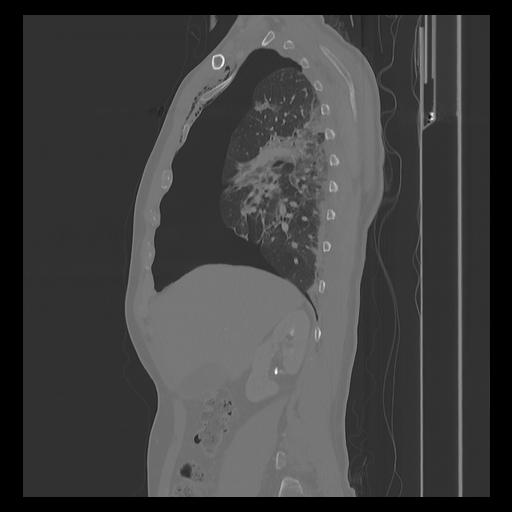

33 PULMON,CE,Sagittal,3.000,PULMON,Sagittal,